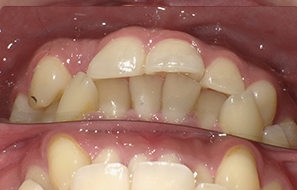

外面拔完時常術後唇麻舌麻,本院發生趨近於零